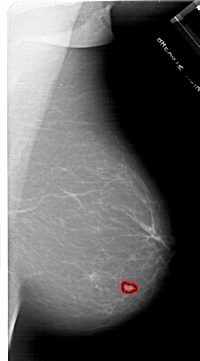

A_1716_1.RIGHT_CC

RIGHT_CC LINES 6076 PIXELS_PER_LINE 3571 BITS_PER_PIXEL 12 RESOLUTION 43.5 OVERLAY

FILE: A_1716_1.RIGHT_CC.OVERLAY

TOTAL_ABNORMALITIES 1

ABNORMALITY 1

LESION_TYPE MASS SHAPE LOBULATED MARGINS MICROLOBULATED

ASSESSMENT 4

SUBTLETY 4

PATHOLOGY BENIGN

TOTAL_OUTLINES 1

BOUNDARY